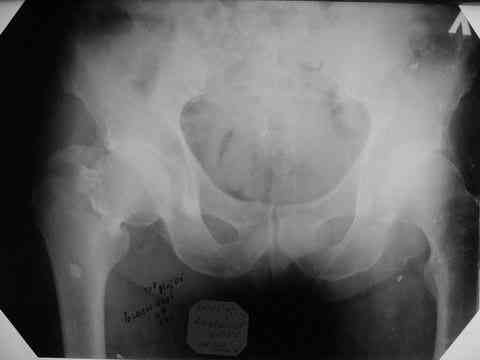

Все-таки хочу поделиться раз затронулась тема, может кому-нибудь и сгодиться. Это пример из области скорее трудноудаляемой. Пациент 50 лет, травма (низкоэнергетическая) 1,5 года назад. Оперирован через неделю (винт отечественный). Через 4 месяца выполнен контрольный снимок, сразу же возник вопрос: почему винт не телескопировался? Вопрос в общем-то так и остался без ответа.

При удалении (наркоз) после неимоверных усилий пришлось выкрутить фиксатор единым блоком и только тут все встало на свои места. См. фото.